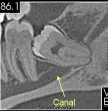

CONHEÇA NOSSA ROTINA CIRÚRGICA